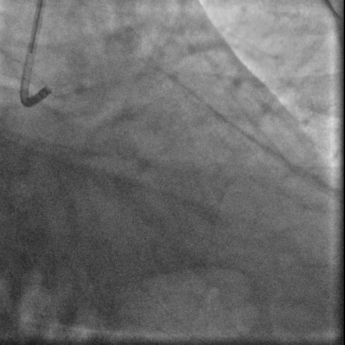

冠脉造影:

右足

右头